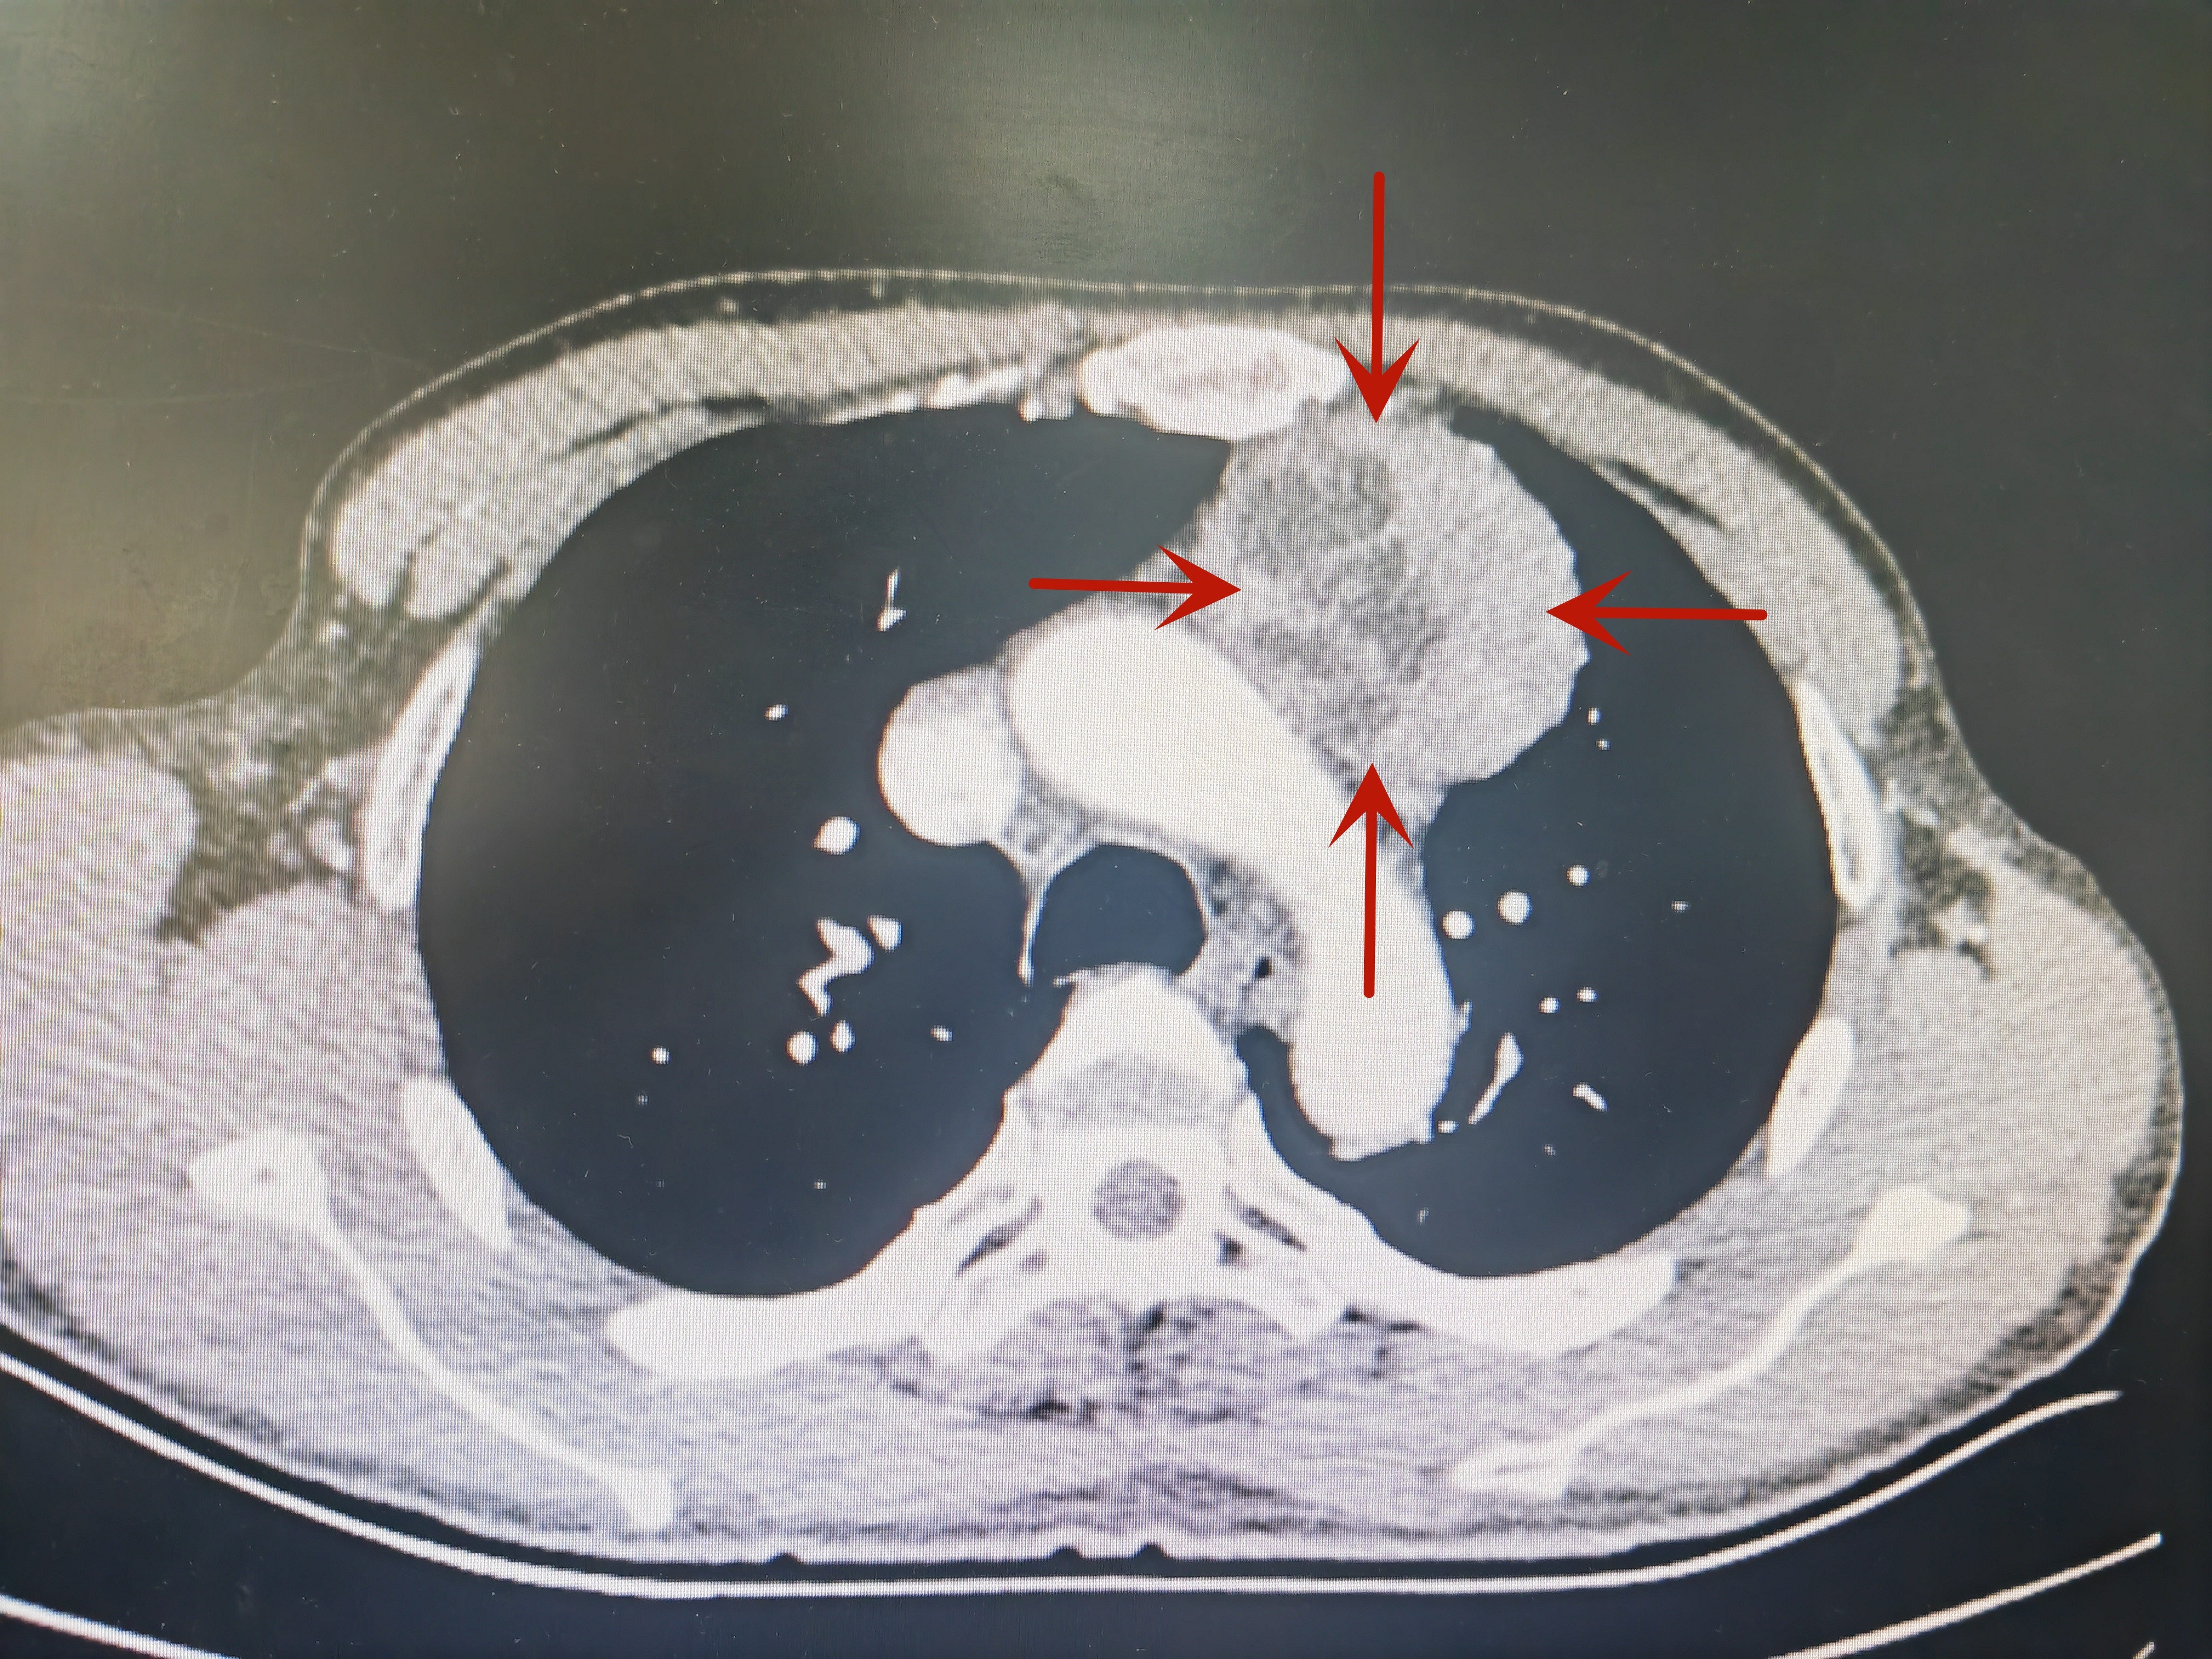

患者陈先生,57岁,因“体检发现纵隔肿物3月余”前往我院就诊,行胸部CT检查示:前上纵隔站位,考虑胸腺瘤。 入科后,杨旺盛主任及其团队进行了反复阅片和多次讨论,由于肿瘤体积大,传统经胸部入路胸腔镜手术视野受限,难以完整分离及切除,而开胸手术由胸骨正中劈开入路,创伤大,术后疼痛明显且恢复慢、并发症多,经过慎密术前分析,并征求家属同意,最终决定行剑突下入路胸腔镜纵隔肿瘤切除术。

红色箭头指向为病变部位↑